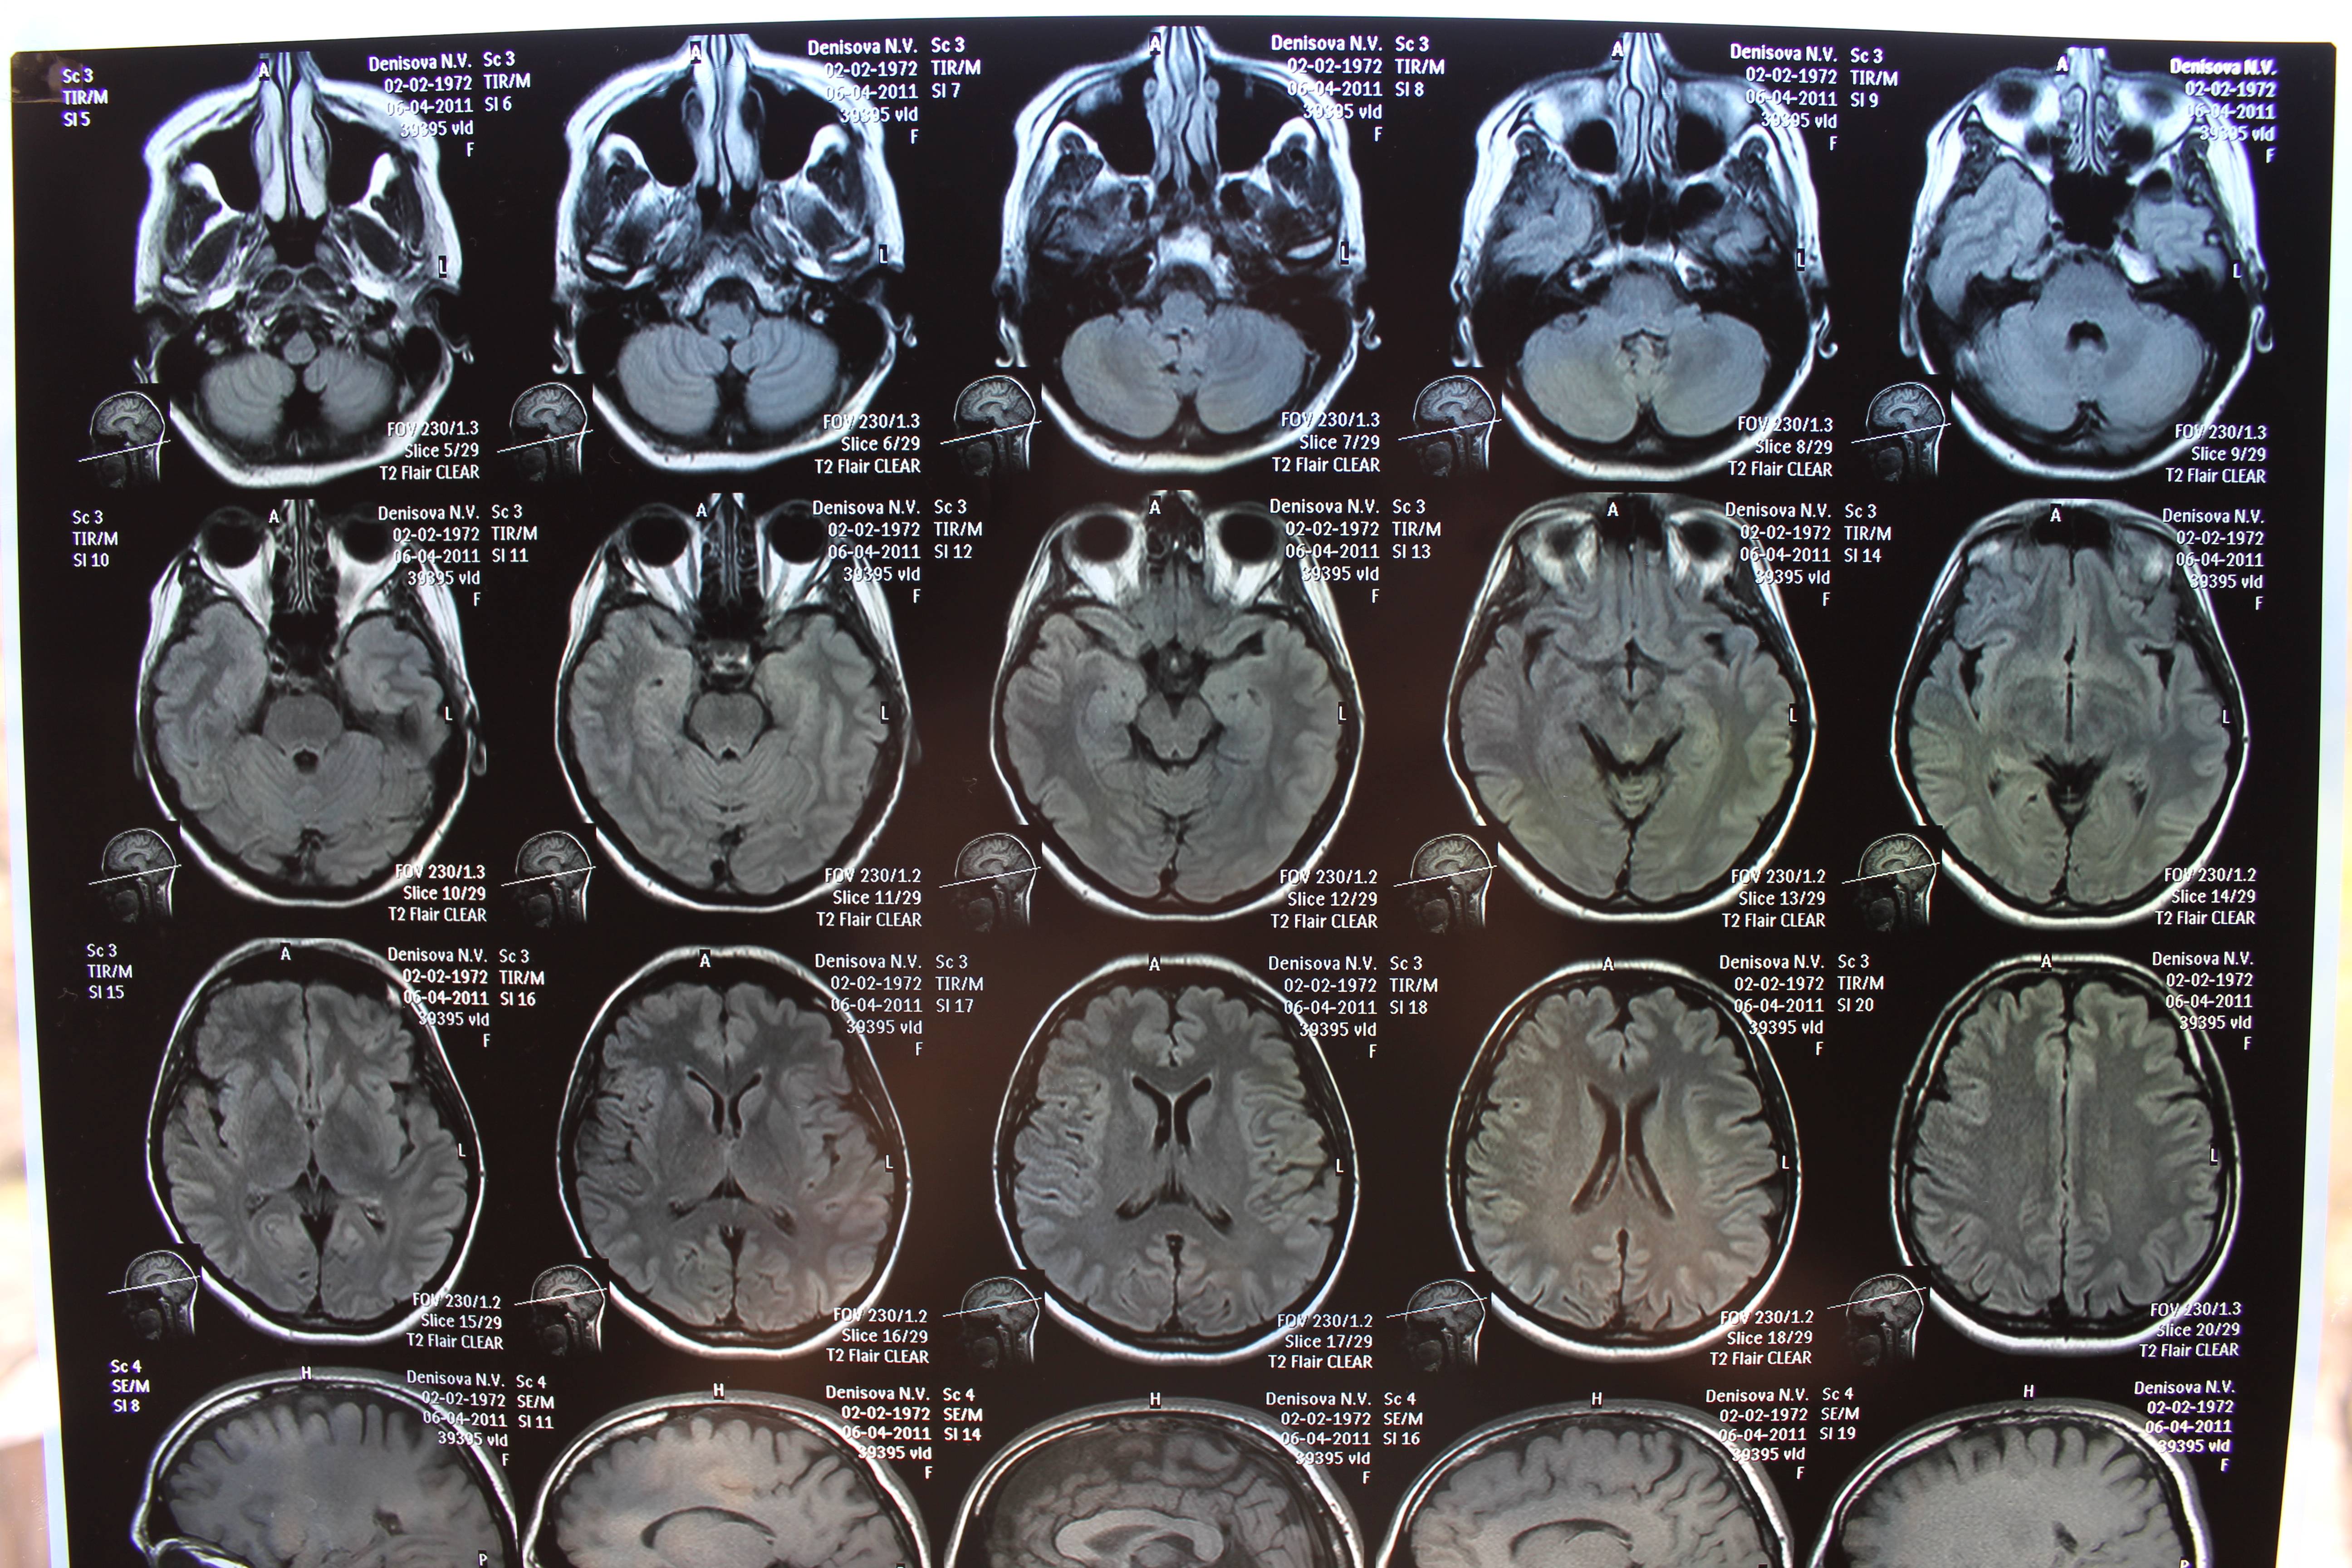

В этом разделе вы найдете примеры снимков МРТ мозга в передней проекции, полезные советы для подготовки к обследованию, а также узнаете, что можно увидеть на таких изображениях.

МРТ головного мозга, что позволяет выявить?

Что показывает МРТ головного мозга

Что скрывает МРТ головного мозга